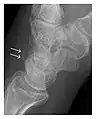

Figure 6: Subtle anterior talar fracture in a 39-year-old man presenting with ankle pain after a fall. (a) Anteroposterior radiograph shows a subtle oblique radiolucent line through the talus (white arrows). (b) Sagittal CT reformation confirms the presence of an anterior talar fracture with cortical offset (black arrow). Avulsion fractures, which consist of a detached bone fragment resulting from a ligament or tendon pulling away from the bone, may also present with subtle radiographic signs. Tiny osseous fragments near the presumed attachment site of a ligament suggest this diagnosis. Common sites are the lateral tibial plateau (the Segond fracture), the spinal tuberosity of the tibia resulting from anterior cruciate ligament avulsion, and the ischial tuberosity.[1]

The greater tuberosity of the humerus is also an illustrative location of occult fractures. The osseous injury may follow seizures, glenohumeral dislocation, forced abduction, or direct impaction. They are commonly discovered on MRI in symptomatic patients with suspicion of rotator cuff tear. Coronal images are best suited for detection. They appear as crescentic oblique lines surrounded by a bone marrow edema pattern (Figure 5). The rotator cuff must be inspected since associated ligamentous lesions are common. In the ankle, malleoli and tarsal bones should be checked carefully for any cortical disruptions and radiolucent lines that may reveal a fracture. Awareness of the exact location of the pain will help direct the attention of the interpreter when searching for very subtle signs of fracture (Figure 6).[1]